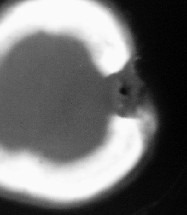

在临床表现上,骨髓炎又分为急性骨髓炎和慢性骨髓炎。急性骨髓炎主要以破坏坏死为主,慢性骨髓炎主要以炎性增生为主,不管是哪一种骨髓炎,都是要非常谨慎的去治疗的,如果没有在初期得到很好的治疗,导致伤病恶化,就会使后期的治疗过程变得艰巨,因为骨髓炎形成的窦道是很恐怖的,开始时可能只有一个小小的窦道,这时候没有得到有效的治疗,就会恶化扩大,致使患处大面积的溃破。